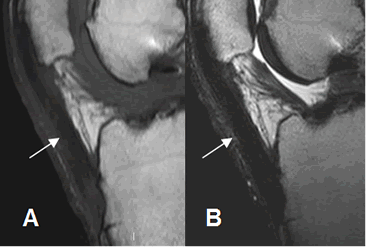

Fig 150. Tendinitis crónica del patelar.

A: RM sagital en T1 y B: RM sagital en T2. Tendón patelar engrosado e hipointenso, como resultado de inflamación crónica.